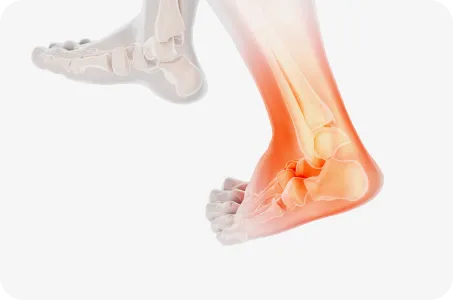

발목염좌

습관성 발목염좌는 일상생활이나 운동을 할 때 발목을 자주 접질리는 증상입니다.

발목관절을 지지하고 있는 인대에 비정상적인 외부 힘이 가해져 손상되거나 과하게 긴장되어 심한 경우에는 인대가 끊어진 상태를 말합니다.

원인

• 발목을 심하게 비틀리거나 접질렀을 때

발목 관절을 지지하는 인대들의 손상으로,

만성 발목염좌로 이환될 수 있습니다.